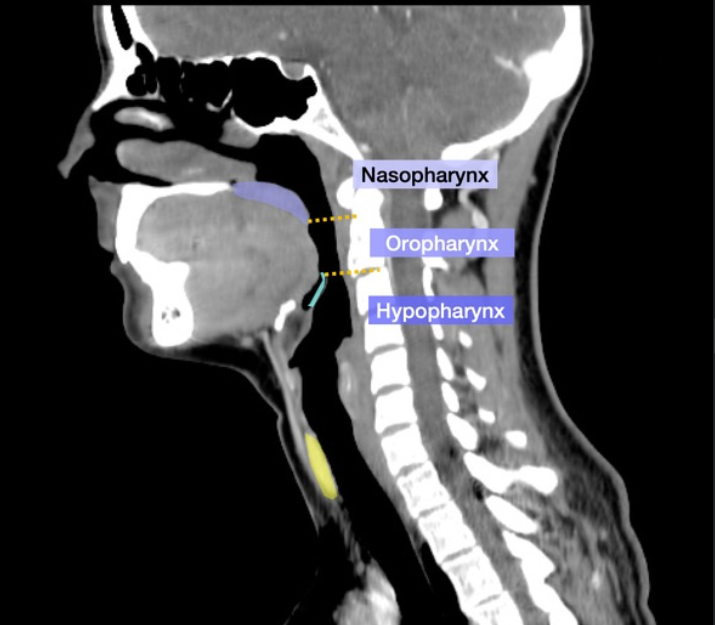

Please label